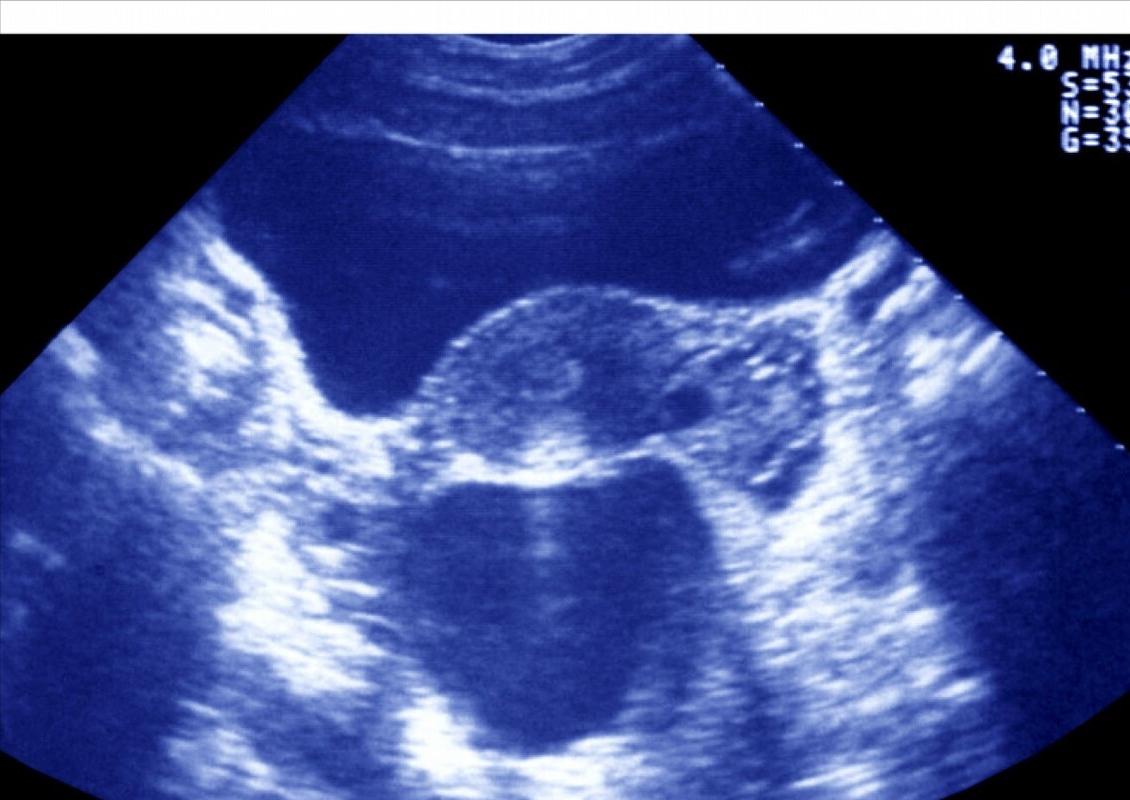

摘要:本篇文章將全面解析輸卵管積水的消除方法。針對輸卵管積水問題,我們將探討有效的治療措施,幫助患者解決這一難題。內(nèi)容包括藥物治療、手術(shù)治療以及生活調(diào)理等方面的介紹,旨在為廣大患者提供有效的積水消除途徑。通過本文,讀者可以了解到如何消除輸卵管積水,恢復(fù)身體健康。

本文將詳細(xì)介紹輸卵管積水的原因、癥狀及消除積水的方法,通過合理的飲食調(diào)整、藥物治療、物理治療以及手術(shù)治療,幫助患者了解并應(yīng)對輸卵管積水問題。

輸卵管積水是一種常見的婦科疾病,可能導(dǎo)致女性生育能力受損,本文將全面解析輸卵管積水消除積水的方法,幫助患者了解并應(yīng)對這一疾病。